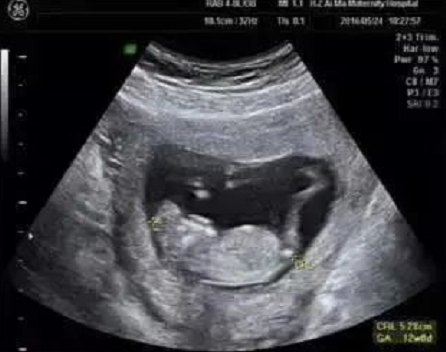

艾玛妇产超声专家团队,在为孕妈妈们做NT检查的同时,对于胎儿的结构也进行了详细的检查,并且发现了多例胎儿严重结构缺陷。

检查选在孕11~13周+6天进行,相当于头臀长45-84mm时测量,超过84mm检查结果会不准确。

NT增厚越明显,胎儿异常机会就越高,异常程度也会越严重。一般正常的NT厚度不能大于3mm,超过3mm表示NT增厚,存在异常可能。

NT异常增厚的主要原因,可能与胎儿染色体异常有关,比较常见的有2 1-三体、18-三体、13-三体综合征等;也可能是胎儿结构畸形,比如说心脏、骨骼系统发育的异常,但是相对于染色体异常来说,结构畸形或其他原因导致NT增厚占比较小。

另外,还有很多宝宝NT增厚是找不到原因的,如果宝宝染色体是正常的、结构是正常的,那么增厚的NT值会随着孕周的增长慢慢消失、恢复正常,须重视产检复查。